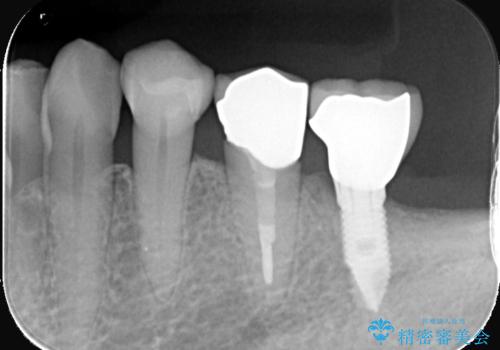

左下4番の歯頚部に知覚過敏症状を認めました。

5級窩洞のコンポジットレジン修復を過去に行ったおり、そのレジンも一部欠けてしまっている状態でした。

咬合力、食いしばりが強く他の歯にも知覚過敏症状が出ているような口腔内で、審美性良く劣化しない丈夫な修復を希望されたため、セラミッククラウンでの治療となりました。